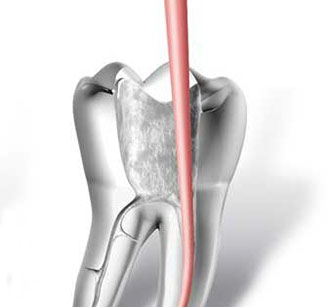

• accesso alla camera pulpare mediante frese diamantate

• asportazione della polpa e sagomatura dello spazio endodontico con strumenti meccanici (in nichel-titanio), con l'ausilio della detersione del canale radicolare (acqua ossigenata, ipoclorito di Sodio, calcio-chelanti)